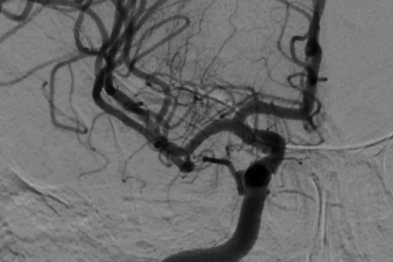

突破生命禁区,再筑健康防线——阳光融和医院消化内科成功实施高难度 TIPS 手术